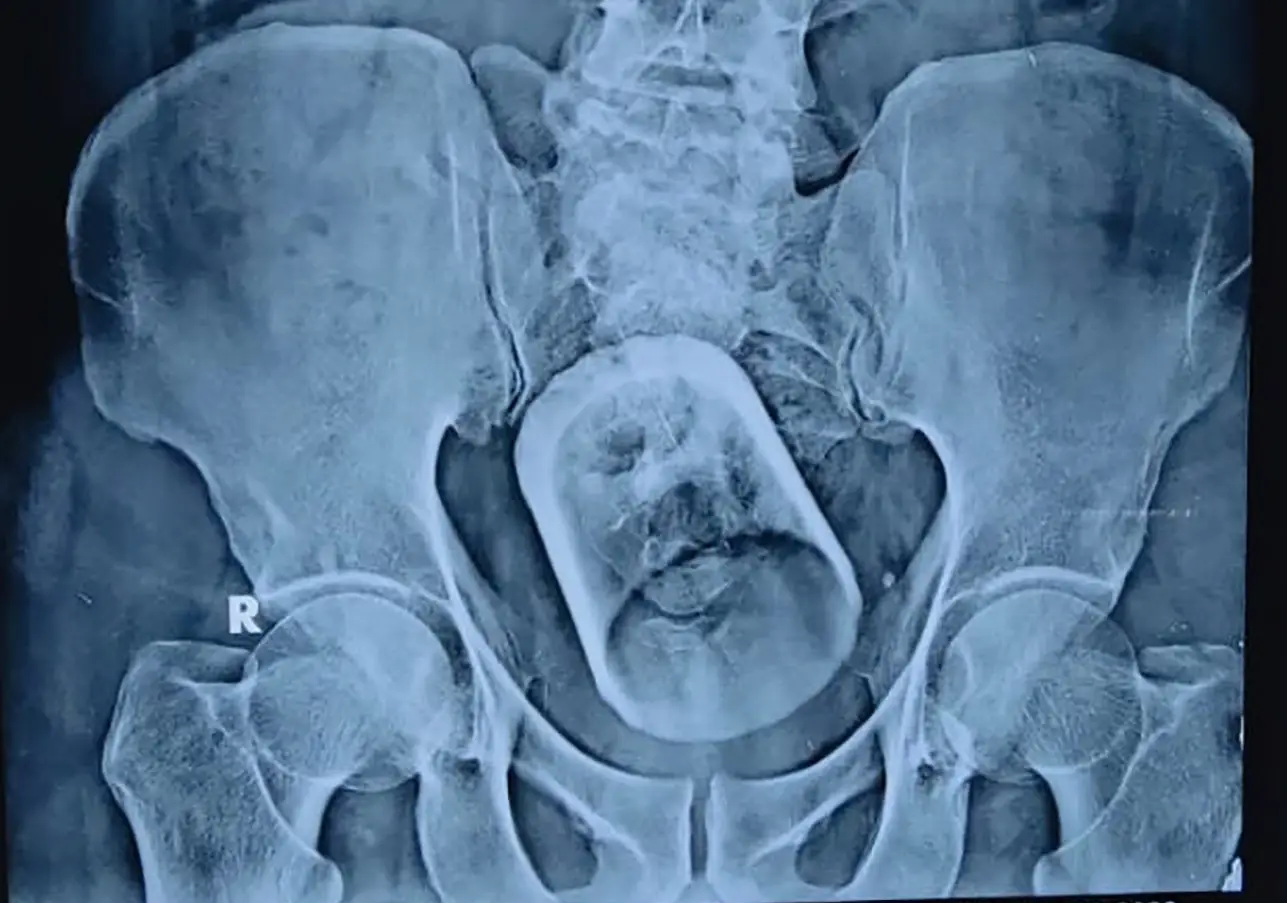

The patient was admitted to a hospital in Bihar, India, with constipation and severe abdominal pain.

He underwent an ultrasound and X-ray, in which doctors located a ‘serious disturbance’ in his intestines.

Much to their shock, that ‘disturbance’ turned out to be a whole glass.

Doctors tried to remove the glass from the rectum with an endoscopic procedure, but had no such luck; they had no choice but to operate on the man to finally remove it.